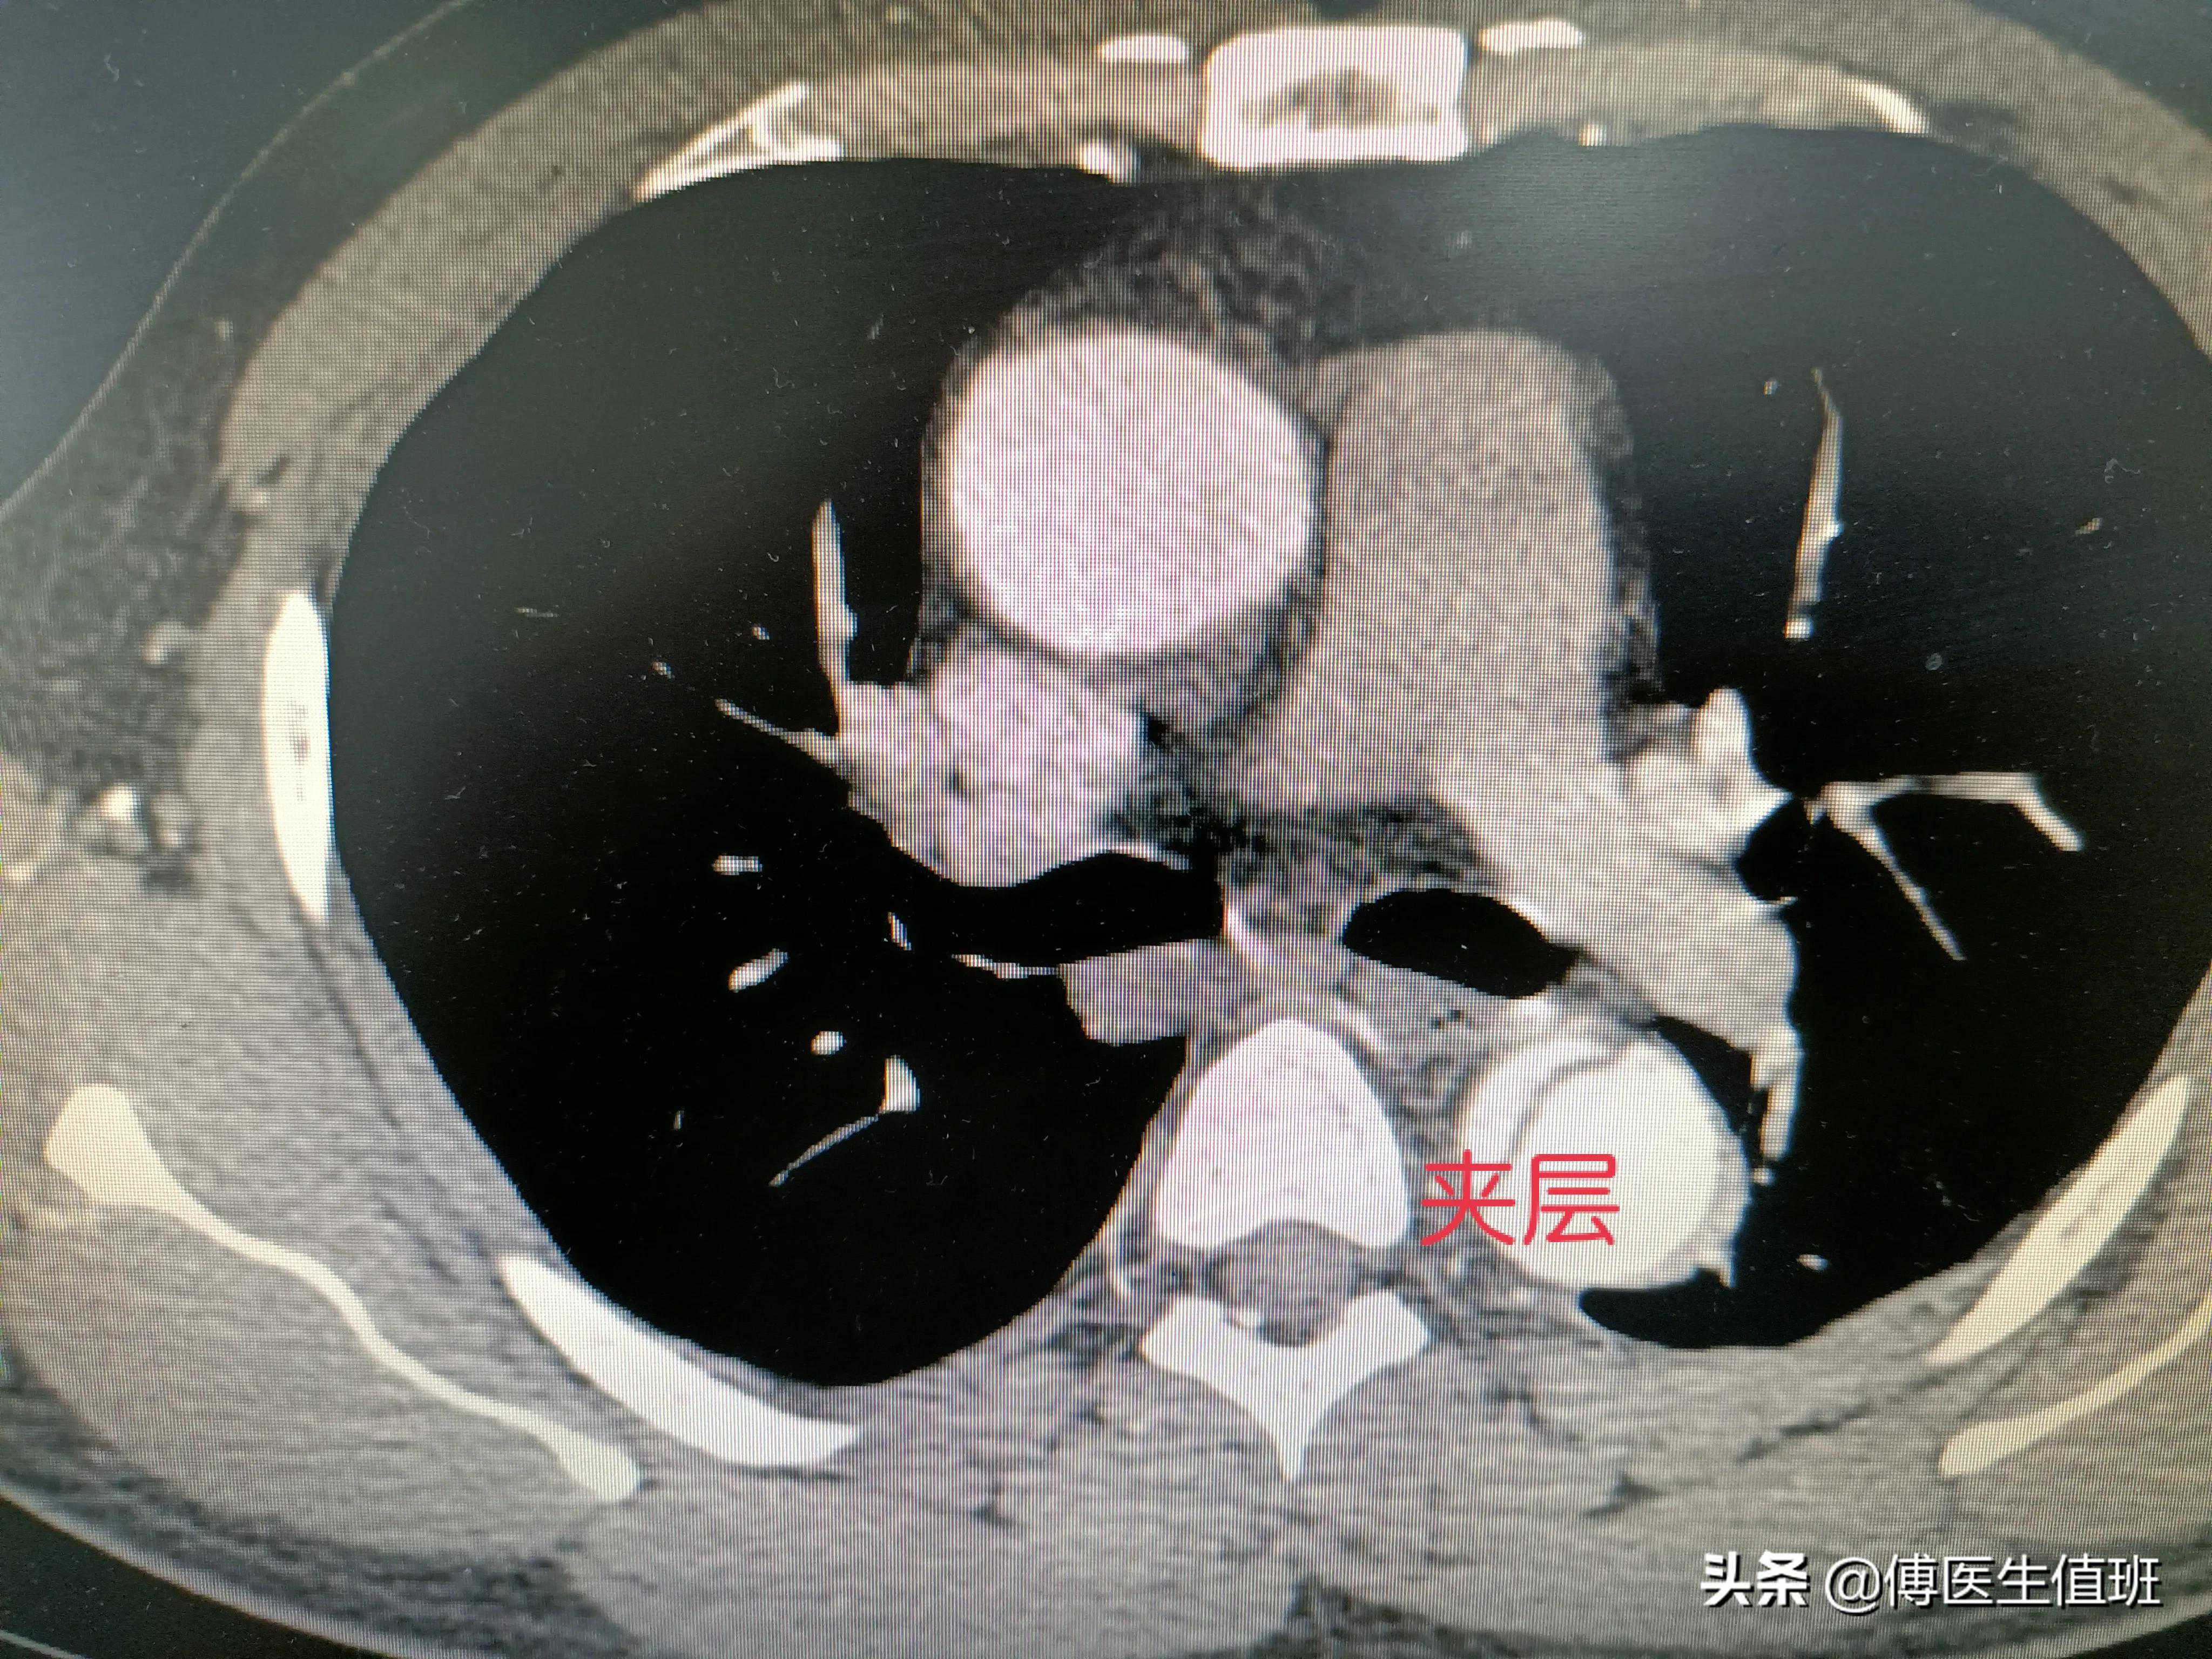

夹层?

主动脉明显增粗,应该是夹层,你看这里,主动脉壁两个层面,没错,是主动脉夹层。

属于哪个类型的主动脉夹层?

CT平扫判断困难,需要做增强扫描。CT室医师说。

主动脉走形迂曲、部分增宽,原发破口位于左锁骨下动脉远端,将主动脉分为两个腔,夹层累计大部分胸降主动脉和腹主动脉,右侧肾动脉起自于假腔,左侧肾动脉由真腔供血,肠系膜上动脉由真腔供血,腹腔干由真假腔供血。范围太广了,一直到腹主动脉全部撕裂。CT室医师说,属于IIIb型。